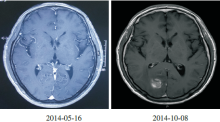

患者, 男性, 70岁, 因“ 肺癌术后4个月, 头痛呕吐1周” 于2014-10-06入院。患者2014年5月因咳嗽、痰中带血就诊于外院, 2014-05-16胸部+上腹部增强CT提示:右肺下叶肿物, 大小约21 mm× 5 mm, 纵隔淋巴结未见肿大; 头颅MRI提示:双侧额顶叶白质多发缺血灶, 副鼻窦炎; 支气管镜提示:右下叶基底段见出血, 盲检未发现癌细胞。2014-05-28 电视胸腔镜手术切除右下肺叶+纵隔淋巴结清扫术, 病理提示:中至低分化腺癌, 癌组织未侵犯脏层胸膜, 可见脉管内癌栓, 未见神经束侵犯, 支气管残端未见癌, R2(0/3)、R4(0/1)、7(0/2)、11(0/6)、12(0/1)、13(0/1); CK7(+), TTF-1(+), CK5/6(-), P63部分细胞弱阳性; 术后诊断为右下肺中低分化腺癌 (pT1bN0M0, Ⅰ a期); 分子病理:EGFR(测序法)阴性, ALK(FISH)阴性, c-MET(FISH)未见扩增; ROS1(FISH)阴性, K-ras阴性, P-TEN(FISH)无缺失。2014-10-02 出现头痛、呕吐, 2014-10-08收入我院。既往史:高血压病史20余年(3级, 极高危); 无吸烟史和粉尘接触史; 无肿瘤家族史。体格检查: T: 36.5℃, P:92 次/分, R: 20 次/分, BP: 142/90 mmHg, PS=1, 全身浅表淋巴结未触及, 头面部无水肿, Horner 征阴性, 上腔静脉综合征阴性, Pancoast 征阴性, 胸廓无畸形, 双肺呼吸音清, 未闻及干湿罗音, 脊柱四肢无异常, 关节无肿痛, 无杵状指。神经系统检查无异常。辅助检查:2014-10-08胸片:右肺术后改变, 右侧胸膜增厚、少量胸腔积液; 2014-10-08 头颅MRI:右枕叶可见类圆形异常信号灶, 约20 mm× 18 mm, 病变周围有脑水肿。见图1。

刘春玲(放射科主治医师):患者2014-05-16在外院行头颅MRI检查, 从影像学来看未见明确的转移病灶, 而在2014-10-08头颅MRI中可以看到右侧枕叶新出现病灶, 在T1相呈高信号, 可能有出血情况, 周围伴有水肿, 结合患者既往肺癌病史, 考虑为脑转移。见图2。